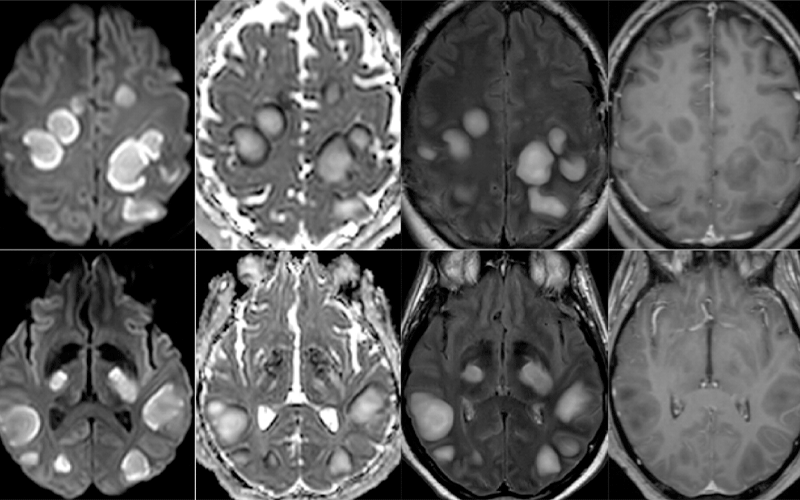

Brain Mri Findings In Covid 19

Multi Institutional Study Looks At Brain Mri Findings In Covid 19